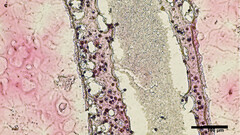

Scientists from the University of British Columbia (UBC) have managed to 3D-print replicas of sperm-producing tubular structures made from viable testicular cells. The bioprinting material was collected via biopsying testicular stem cells from patients who have non-obstructive azoospermia (NOA), the heaviest form of male infertility. Those protocells were then grown and multiplied before 3D-printing them into a tubular structure similar to the sperm-making ones located in human testicles.

Not only was the bioprinting method successful in terms of cell survival, but after 12 days the tubes were examined and the material "had matured into several of the specialized cells involved in sperm production." Furthermore, the faux testicular tubes "were showing a significant improvement in spermatogonial stem cell maintenance – both early signs of sperm producing capabilities," says the report. According to the the study's lead researcher, UBC urology assistant professor Dr. Ryan Flannigan: